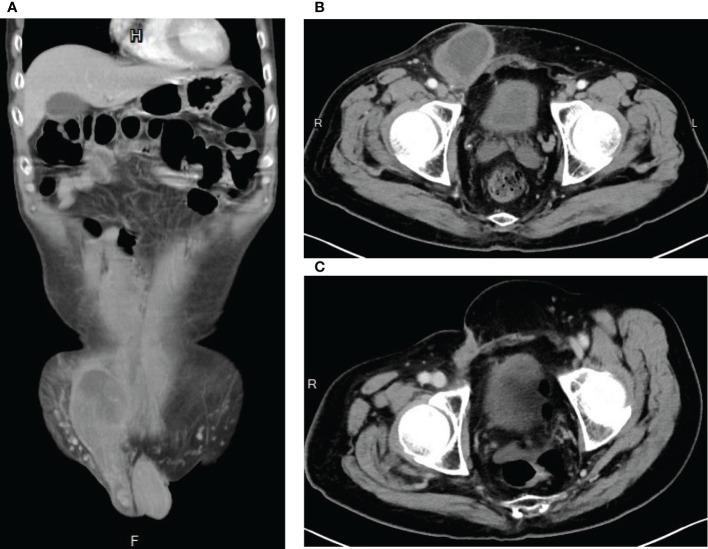

A 55-year-old Han Chinese male presented to the general surgery department with a one-year history of abdominal fullness and a one-week history of palpable right inguinal mass. At first, he was diagnosed with incarcerated inguinal hernia. However, abdominal computer tomography (CT) and biopsy confirmed his final diagnosis to be retroperitoneal well-differentiated liposarcoma, cT2bN0M0, stage IIb. The tumor, which measured 44.5cm in maximum diameter, was too large for primary surgical resection. Neoadjuvant radiotherapy with 70 Gy in 35 fractions was delivered to the tumor, which shrunk the target volume from 6300 cc to 4800 cc, as observed in the middle of the radiotherapy course. The right testicular mass also received 70Gy/35Fx. Conversion surgery was performed after radiotherapy. Unfortunately, due to residual tumor, adjuvant chemotherapy consisting of AIM (ifosfamide, Mesna, and doxorubicin) and MAID (Mesna, doxorubincin, ifosfamide, and dacarbazine) regimens were administered sequentially. Afterward, debulking surgery was conducted, plus another 18 cycles of ifosfamide monotherapy when residual tumor was still seen on CT. Since the completion of ifosfamide chemotherapy, the patient has been cancer free with no evidence of tumor recurrence for more than 26 months.

一名55岁的汉族男性因腹部胀满1年、右腹股沟可触及肿块1周就诊于普通外科。起初,他被诊断为嵌顿性腹股沟疝。然而,腹部计算机断层扫描(CT)和活检最终确诊为腹膜后高分化脂肪肉瘤,cT2bN0M0,IIb期。肿瘤最大直径为44.5cm,太大无法进行一期手术切除。对肿瘤进行了新辅助放疗,分35次给予70Gy,在放疗疗程中期观察到靶体积从6300cc缩小至4800cc。右侧睾丸肿块也接受了70Gy/35次分割的放疗。放疗后进行了转化手术。不幸的是,由于残留肿瘤,先后给予了由AIM(异环磷酰胺、美司钠和阿霉素)和MAID(美司钠、阿霉素、异环磷酰胺和达卡巴嗪)方案组成的辅助化疗。之后,进行了减瘤手术,当CT上仍可见残留肿瘤时,又给予了18个周期的异环磷酰胺单药治疗。自异环磷酰胺化疗完成以来,患者已无癌生存超过26个月,无肿瘤复发迹象。